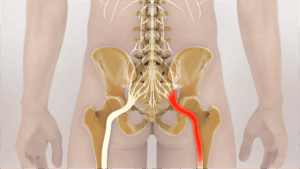

Sciatica pain affects a lot of people, causing discomfort and disrupting everyday life. It’s often described as a sharp pain

Sciatica is becoming increasingly widespread in modern times, affecting everyday activities. It’s the pain that shoots down from your lower

The world of Ayurveda offers a gentle and holistic approach to soothe the discomfort caused by sciatica pain. This ancient

Sciatica pain can make everyday tasks challenging. For those seeking a natural approach to relief, Ayurveda for sciatica offers a